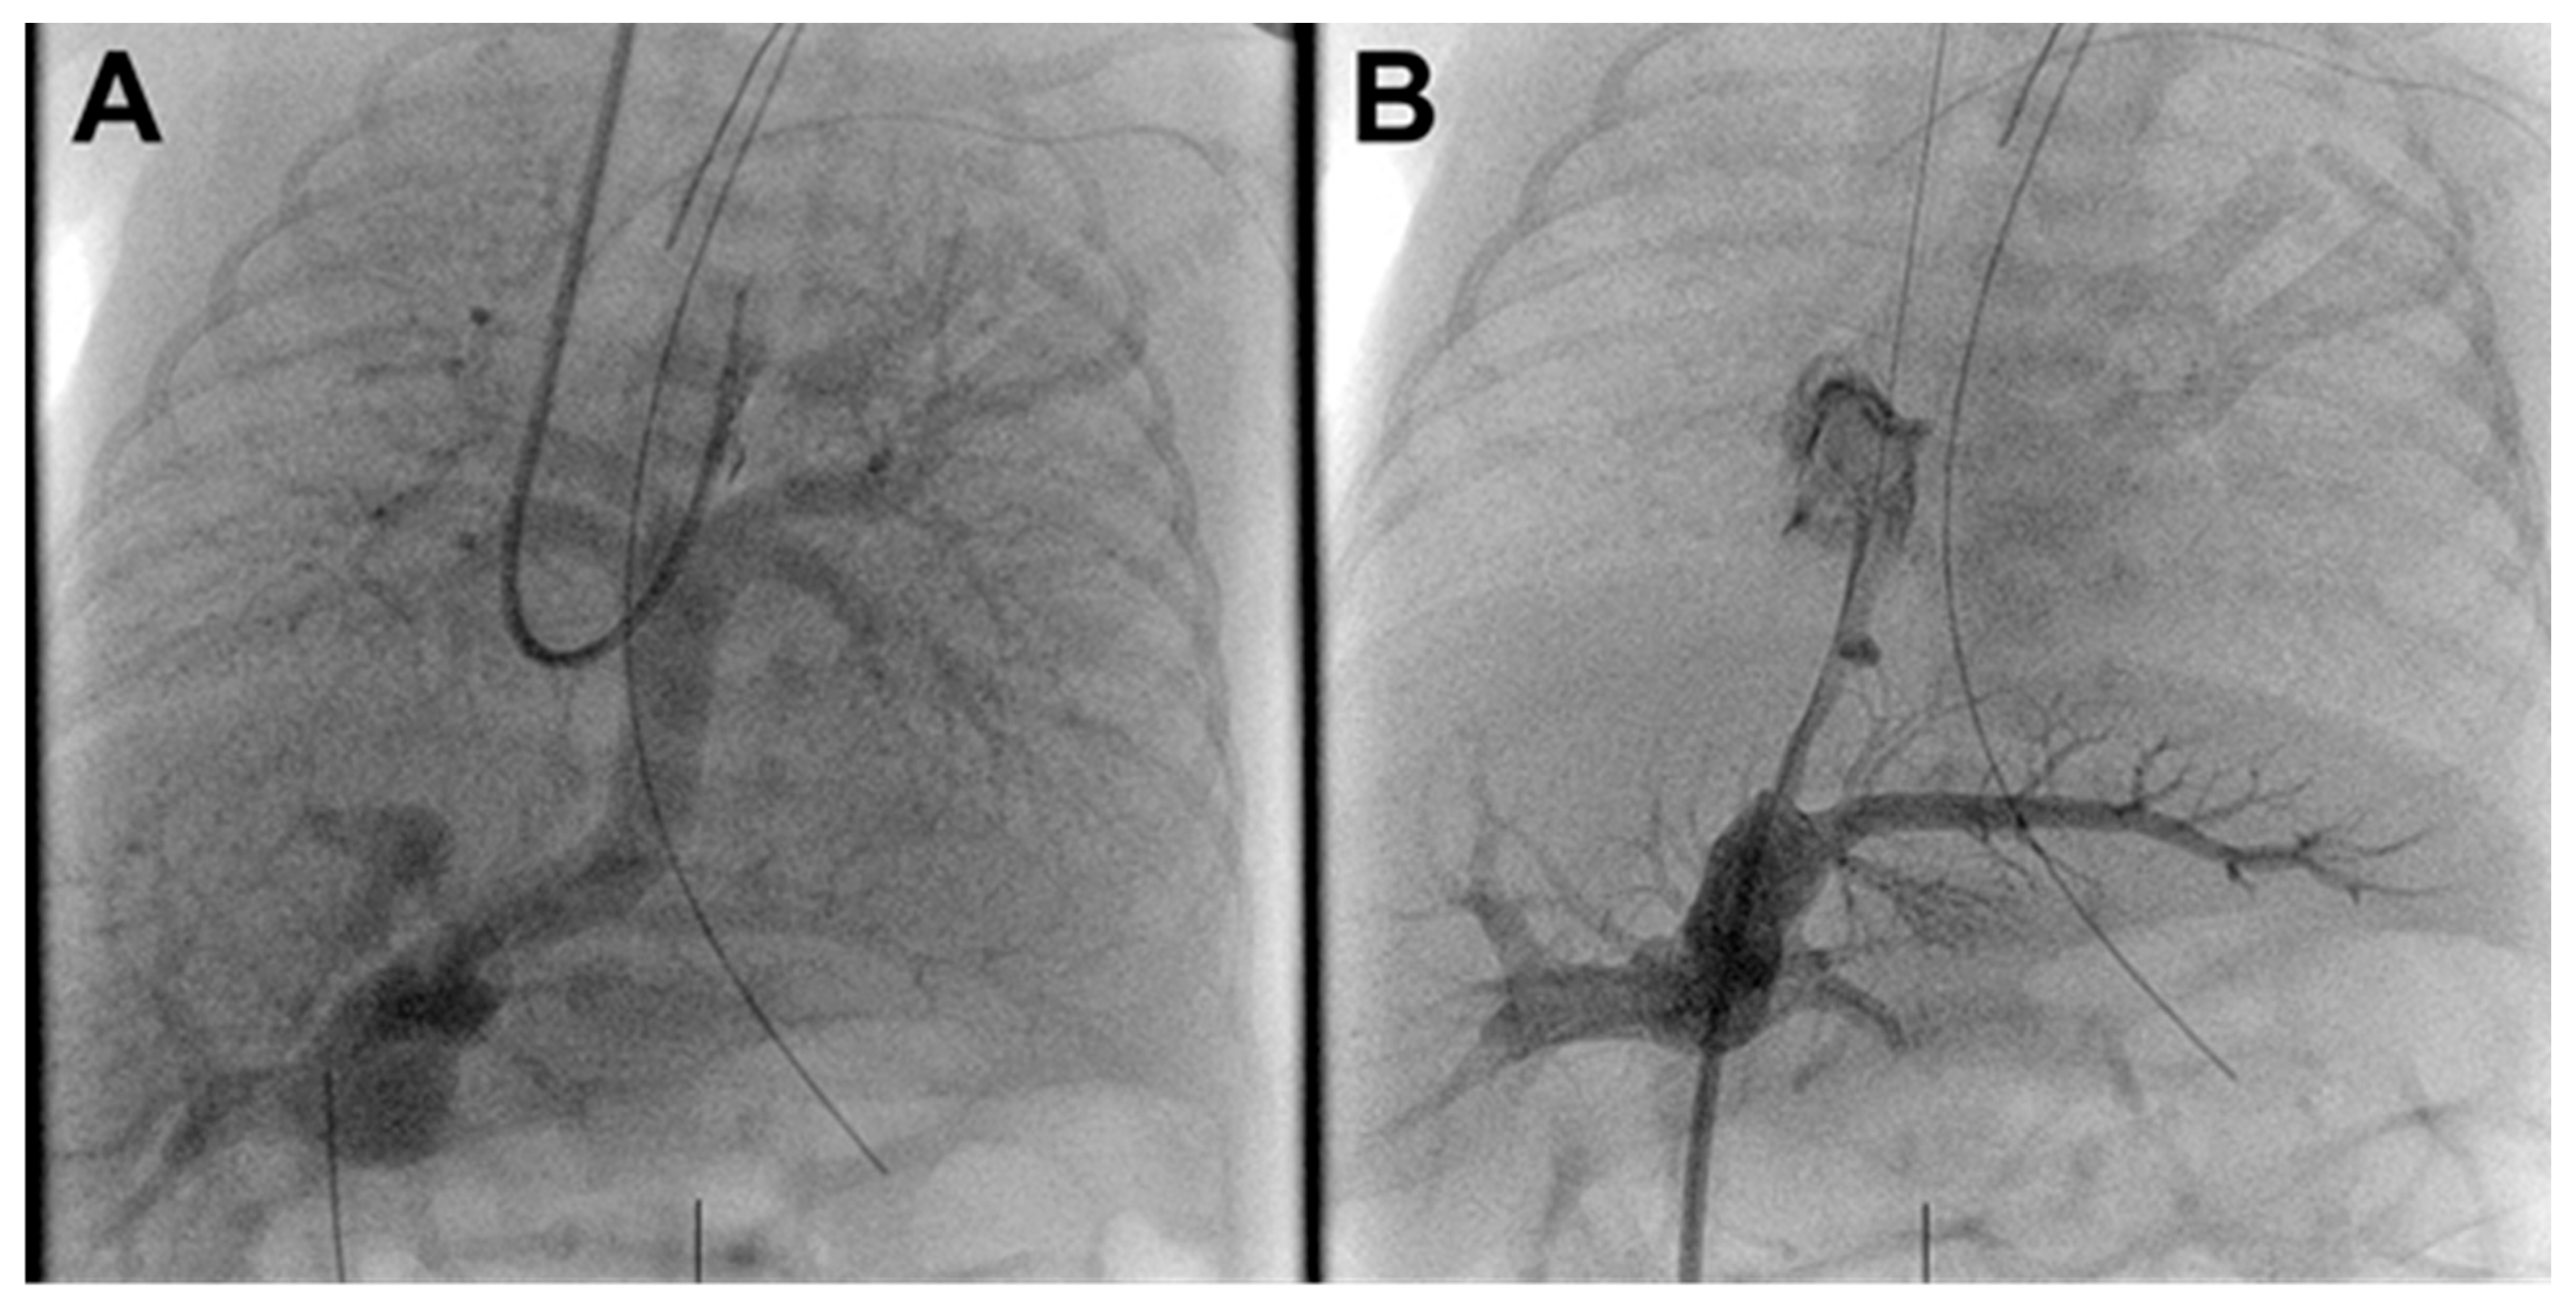

In the catheterization laboratory, her right neck, bilateral groins and the entire umbilical area including the line were prepped and draped in the normal sterile fashion. Using ultrasound guidance, the right internal jugular (IJ) vein was accessed and a 4 Fr sheath was placed. After 50 units of heparin and 30 mg/kg of cefalexin were given, a 4 French Berman angiographic catheter was advanced into the pulmonary arteries (PA). Limited hemodynamics demonstrated PA systolic pressures 70% systemic and angiography confirmed infradiaphragmatic TAPVR with mild narrowing at the connection of the vertical vein (VV) to the right portal vein (PV) and no obvious flow through the ductus venosus (DV) back to the right atrium (Fig. 1A, Supplemental Video S1).

The UVC was removed and a 4-French Prelude sheath was advanced through the stenotic DV into the right atrium. Angiography through the sheath confirmed DV and PV anatomy demonstrating a 15 mm long DV narrowing to ~1.2 mm along its entire length (Fig. 1B).

Figure 1: Pre-intervention angiograms. (A). Venous phase pulmonary angiogram demonstrating infradiaphragmatic TAPVR to the portal venous system without vertical vein stenosis. (B). Severe ductus venosus stenosis with filling of the portal venous system.